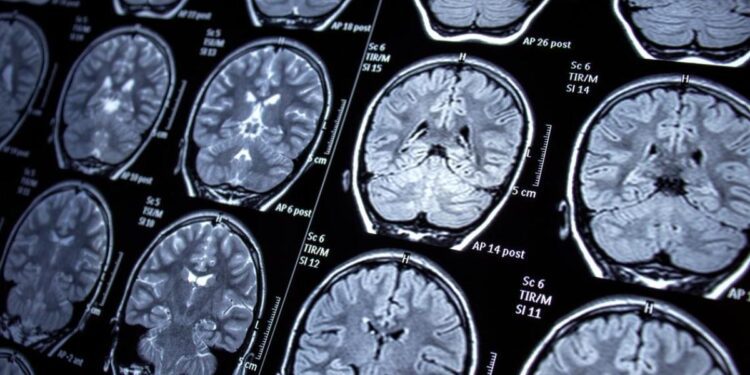

Une découverte majeure dans la recherche sur la maladie d’Alzheimer vient d’éclairer le rôle crucial des cellules immunitaires cérébrales dans cette pathologie dévastatrice. Des scientifiques ont démontré que les microglies présentes dans les cerveaux de personnes atteintes d’Alzheimer présentent des comportements distincts par rapport à celles des individus sains, ouvrant potentiellement la voie à de nouvelles approches thérapeutiques.

L’analyse, menée sur des tissus cérébraux humains, révèle que ces cellules protectrices adoptent plus fréquemment un état pré-inflammatoire, compromettant leur capacité défensive naturelle.